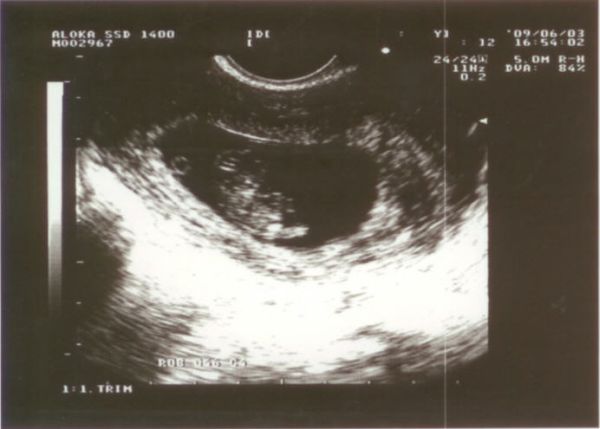

Kép 9 hetesen 1 Kép 9 hetesen 2

Mi a tegnap voltunk a második ultrahangon 9 hetesen. Mostmár elég szépen látszik a baba. Ugy néz ki hogy minden rendben van ( hál Istennek) 22 MM - hosszú. Legközelebb 3 hét mulva 12 hetesen megyünk.

Nahát, már egész babaformájú! :D Nem csak olyan kis paca, hanem kivehető a feje is.